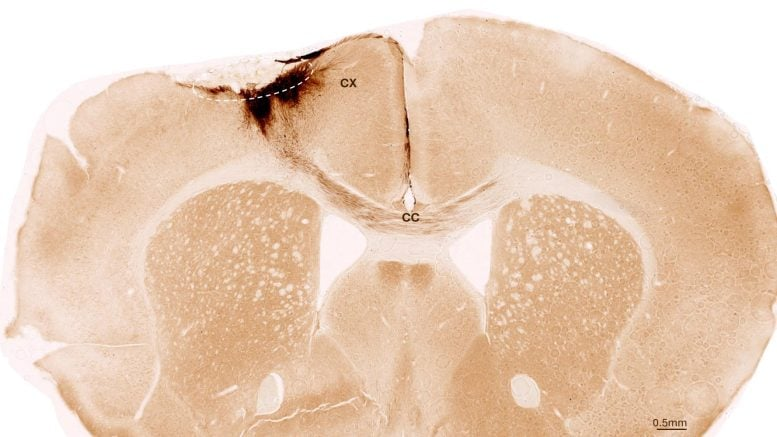

Coronal section of a mouse brain after stroke and neural stem cell transplantation, showing transplanted cell neurites extending across both hemispheres. Credit: University of Zurich.

The results were astonishing. The transplanted stem cells survived the entire observation period and transformed primarily into neurons, rather than support cells. More importantly, these new neurons connected with the mice’s existing brain cells, forming communication pathways similar to natural brain circuits.

This wasn’t just a visual observation—scientists verified neural activity and signaling between the transplanted cells and the host neurons. These new neurons weren’t passive passengers; they were actively integrating and helping rebuild damaged connections.